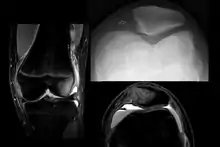

To assess the knee, a clinician can perform the patellar apprehension test by moving the patella back and forth while the people flexes the knee at approximately 30 degrees.[14]

The people can do the patella tracking assessment by making a single leg squat and standing, or by lying on his or her back with knee extended from flexed position. A patella that slips laterally on early flexion is called the J sign, and indicates imbalance between the VMO and lateral structures.[15]

On X-ray, with skyline projections, dislocations are readily diagnosed. In borderline cases of subluxation, the following measurements can be helpful:

- The lateral patellofemoral angle, formed by:[16]

- A line connecting the most anterior points of the medial and lateral facets of the trochlea.

- A tangent to the lateral facet of the patella.

- With the knee in 20° flexed, this angle should normally open laterally.[16]

- The patellofemoral index is the ratio between the thickness of the medial joint space and the lateral joint space (L). With the knee 20° flexed, it should measure 1.6 or less.[16]